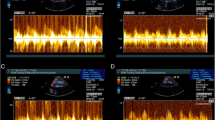

Coronary hemodynamics as a function of LV elastance over a single cardiac cycle. In this diagram, we relate cardiac contraction to coronary blood flow velocity and coronary pressure. a to c are under resting/baseline conditions. Cardiac contraction over one cardiac cycle is represented as elastance (instantaneous LV pressure/volume). This generates a bell-shaped curve seen in a. This starts and ends at end-diastole when LV pressure is minimal and peaks in the center at end-systole. The aim of this plot is to represent LV contraction and relaxation over one cardiac cycle. b This is a simultaneous plot of LV elastance (in a) against coronary blood flow velocity to demonstrate how LV contraction-relaxation impacts coronary flow velocity; this is performed under resting, baseline conditions. c This is a simultaneous plot of LV elastance (from a) against distal coronary pressure measured by the Combowire, to demonstrate how LV contraction-relaxation affects coronary artery pressure. d–f are the same plots after IV adenosine administration; the aim is to abolish autoregulatory processes and maximize vasodilatation to see how this changes the cardiac-coronary interaction D LV elastance plotted against time following adenosine E simultaneous plot of LV elastance (in a) against coronary blood flow velocity to demonstrate how LV contraction-relaxation impacts coronary flow velocity following IV adenosine F simultaneous plot of LV elastance (from a) against distal coronary pressure measured by the Combowire, to demonstrate how LV contraction-relaxation affects coronary artery pressure. U coronary blood flow velocity, ED end-diastole, ED+10 end-diastole + 10ms to identify direction of figure of 8 graph over time, ES end-systole

We then examined the association between left ventricular elastance (contractile properties) and coronary blood flow velocity through one cardiac cycle. Figure 6a demonstrates LV elastance over time through one cardiac cycle at baseline. In Fig. 6b, we plotted coronary blood flow velocity against LV elastance at baseline. This demonstrated a figure of eight curve with coronary flow velocity peaking with minimal elastance, and Fig. 6c demonstrates distal coronary pressure as a transmission of LV elastance. Following administration of IV adenosine, to minimize microvascular resistance, there was an increase in LV elastance (Fig. 6d), and in Fig. 6e, we demonstrate a clear inverse exponential relationship between coronary blood flow velocity and LV elastance.

To examine the association between coronary wave energies and left ventricular pressure-volume, we mapped the timing of the origin and termination of wave energies to the cardiac cycle as measured by the pressure-volume loop during left ventricular contraction and relaxation during resting conditions (Fig. 4). We describe the four main wave energies responsible for acceleration and deceleration of coronary blood flow in relation to the timing of LV contraction and relaxation (Fig. 4b and c). The forward compression wave (FCW) was shown to be generated during isovolumic contraction just prior to aortic valve opening and terminated at peak left ventricular pressure (LV pressure equal to aortic systolic pressure). The backward expansion wave (BEW) was shown to be generated at end-systole (aortic valve closure) and terminated near end-diastole, at the point of minimum left ventricular pressure. The backward compression wave was generated during isovolumic contraction and terminated on aortic valve opening. The forward expansion wave (FEW) was initiated at maximal LV contraction at the point of peak systolic blood pressure and terminated at end-systole (when LV pressure is equal to diastolic blood pressure). The timings of the coronary wave energies including initiation, termination, and peak are presented alongside timings of the major events in the cardiac cycle in Fig. 4d. Wave timings did not change with either exercise or ISDN administration.

Coronary wave energies superimposed on the pressure-volume (PV) loop. a The cardiac cycle depicted as LV pressure (LVP) as function of volume (LVV), the end-diastole (ED), end-systole (ES), and dP/dT max and dP/dTmin (maximal rate of pressure increase and pressure decline, respectively) depicted on the PV loop. b The forward travelling compression wave (FCW) in the coronary artery originates when LV pressure equals aortic diastolic pressure (immediately prior to aortic valve opening) and terminates immediately prior to peak LV pressure. The forward expansion wave (FEW) originates when LV pressure equals aortic systolic pressure (peak LV pressure) and terminates during isovolumic relaxation at the point of dP/dT min (maximal LV rate of relaxation). c The backward compression wave (BCW) originates during isovolumic contraction and terminates immediately after aortic valve opening (when LV pressure exceeds aortic diastolic pressure). The backward expansion wave (BEW) originates on aortic valve closure, at end-systole, and terminates at minimum LV pressure. d Wave generation during the cardiac cycle. The black broken line represents end-systole, with standard deviation (red broken line). ED end-diastole, BCW backward compression wave, FCW forward compression wave, BEW backward expansion wave, ES end-systole, FEW forward expansion wave, ms milliseconds, s start, p peak, e end